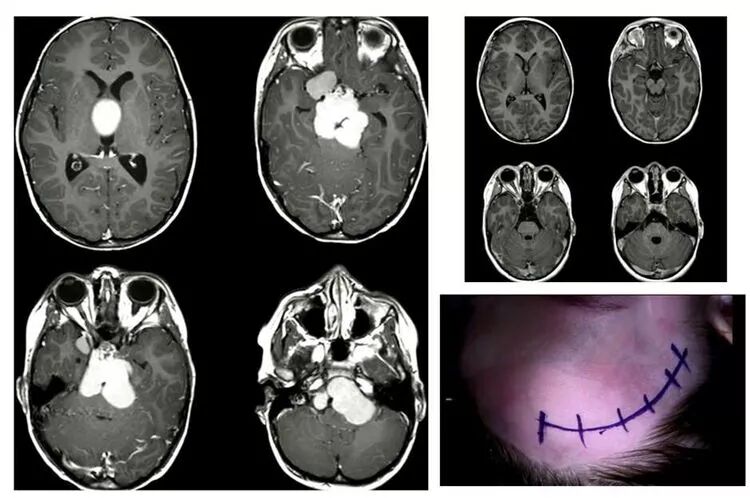

四谈Juha大师之手术艺术。

其一,妙用Sundt clip,救命夹。鞍上脑膜瘤将右侧颈内动脉包裹,术中颈内动脉破裂,出血汹涌,此时应用Sundt clip,救命也。

其二,使用microdoppler,测定血流状态。既要控制出血,又要预防术后大面积脑梗死。也即,既着眼当下(术中出血),也着眼未来(术后梗死)。step by step,步步为赢。

其三,此病例,应用神经内镜技术,也可以进行切除。但是,一旦颈内动脉破裂,则是灾难性的。

除非在打开蝶骨平台前,已经提前将颈内动脉斜坡段磨除显露;除非已经做好颈内动脉颅外段结扎的准备。这样做,虽然控制了出血,但却造成了梗死。

况且,类似病例,在临床实践中,我们是很少提前显露颈内动脉近端的。

颈内动脉破裂出血,那种由内镜转为开颅或介入止血的想法,有时是不切合实际的。因为,我们没有时间。此刻,时间,就是大脑。

其四,成功出色的外科工作,来自于精心的手术设计,以及切实可行的风险应对。